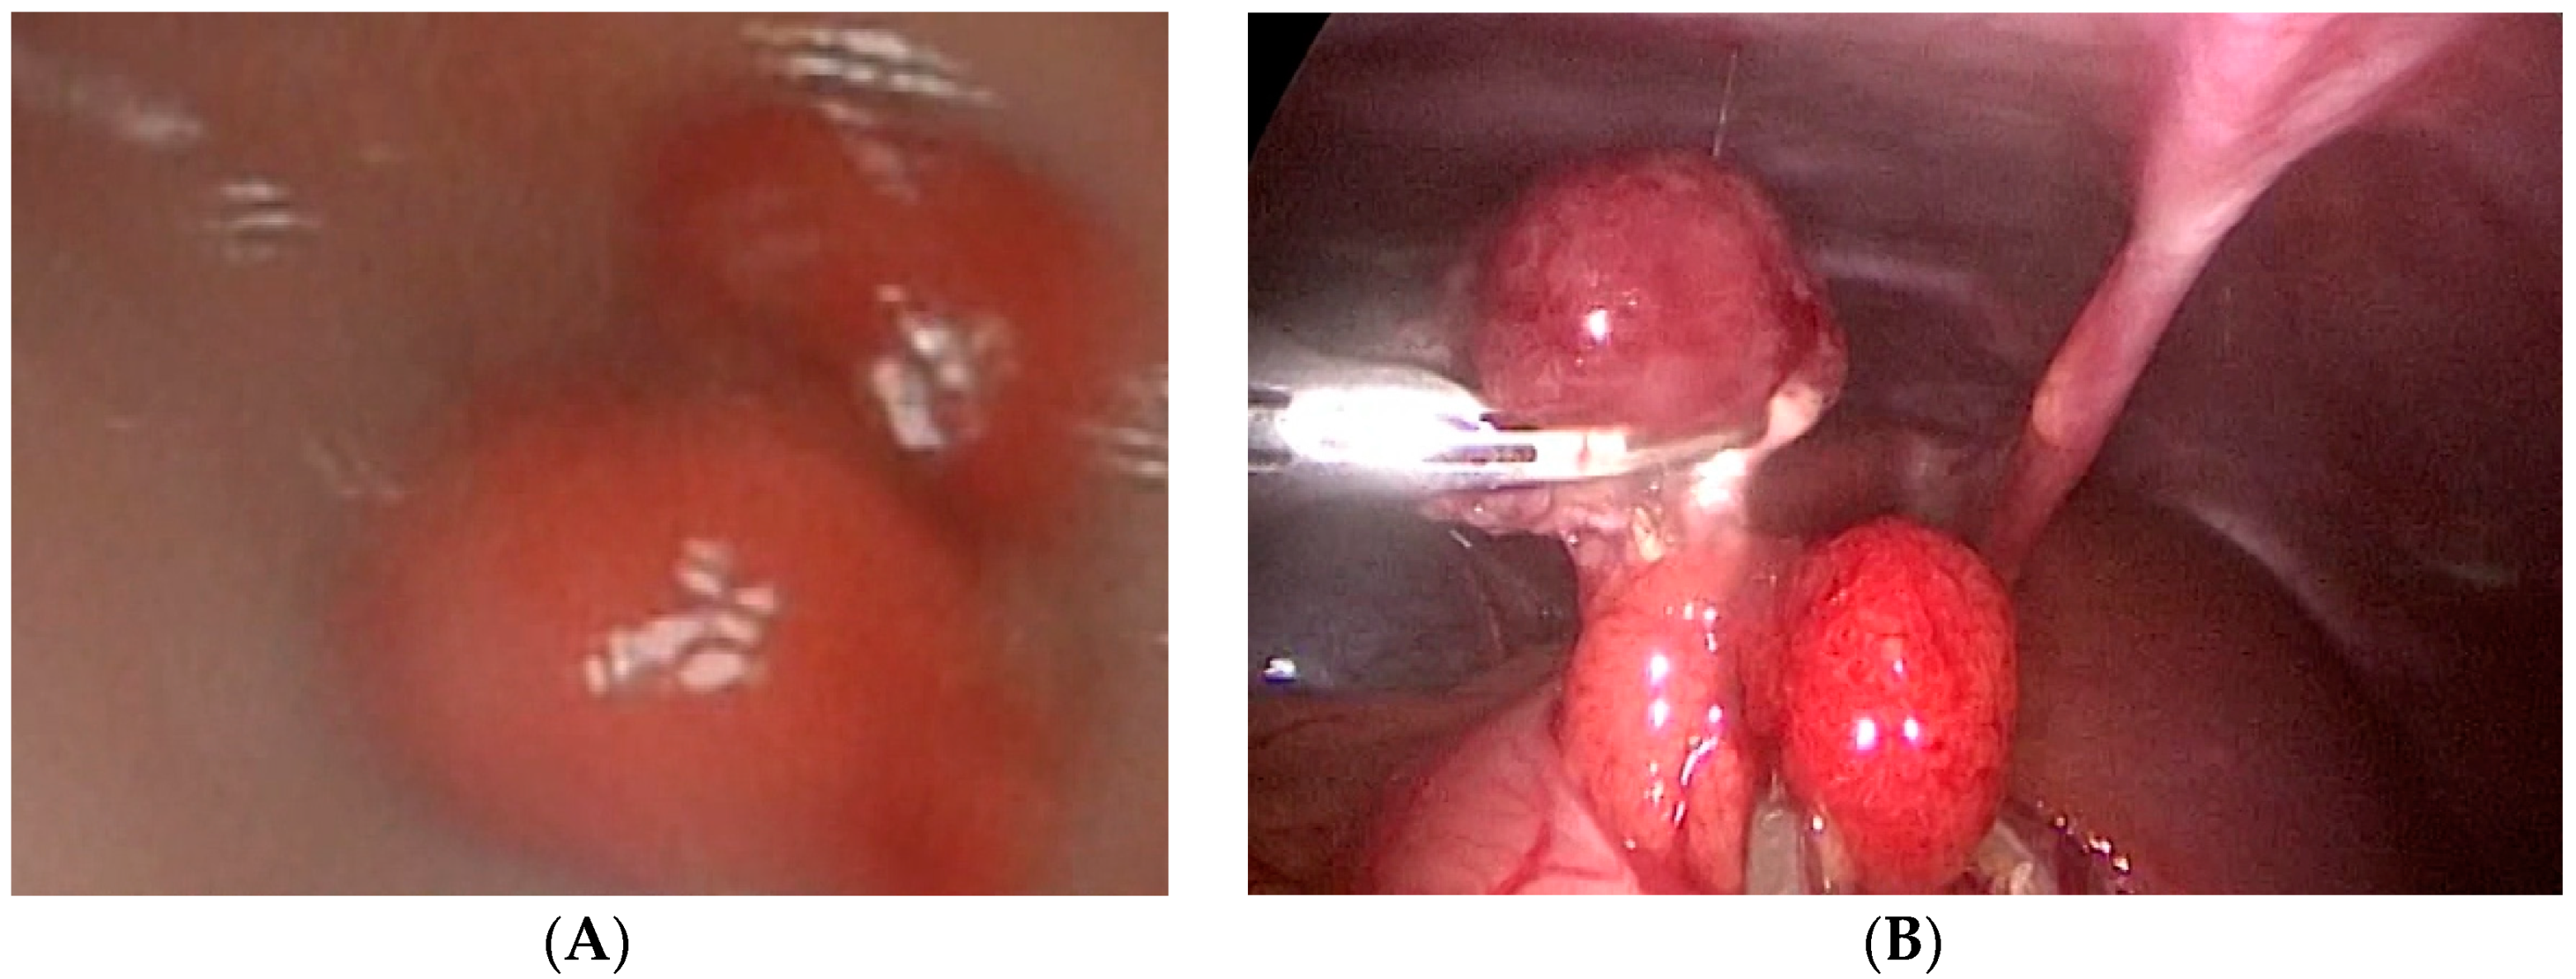

Case number six is a 3-year-old girl who presented with hematemesis and melena. An endoscopy revealed two oval polyps located at the antrum of the stomach with the largest diameters of 1 and 1.5 cm. One of these polyps was bleeding actively and an endoscopic injection hemostasis was conducted. Due to the technical inability, an endoscopic polypectomy was not performed. The next day, a combined laparoscopic–endoscopic “rendezvous” polypectomy was completed. After having polyps endoscopically visualized (Figure 2A), an anterior gastrotomy was performed. A double polypectomy was made using an ultrasonic knife (Figure 2B). The gastric wall was sutured, and the operation was completed with an omentopexy.

Figure 2.

Endoscopic visualization of two polyps and laparoscopic polypectomy. (A) After having polyps endoscopically visualized; (B) A double polypectomy was made using an ultrasonic knife.